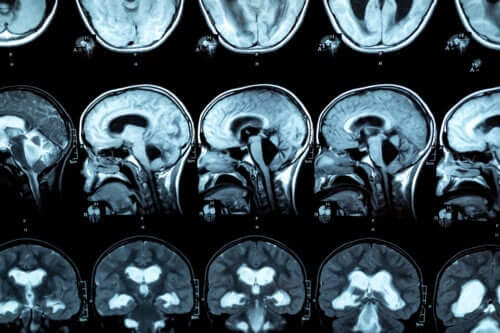

Per la diagnosi di questa patologia viene eseguita una risonanza magnetica, in modo da poter osservare le lesioni nel corpo calloso. Le ricerche indicano che le persone con disturbo da uso di alcol mostrano una riduzione dello spessore anteriore, medio e posteriore del corpo calloso, oltre a variazioni nelle dimensioni del lobo frontale e dei solchi corticali.